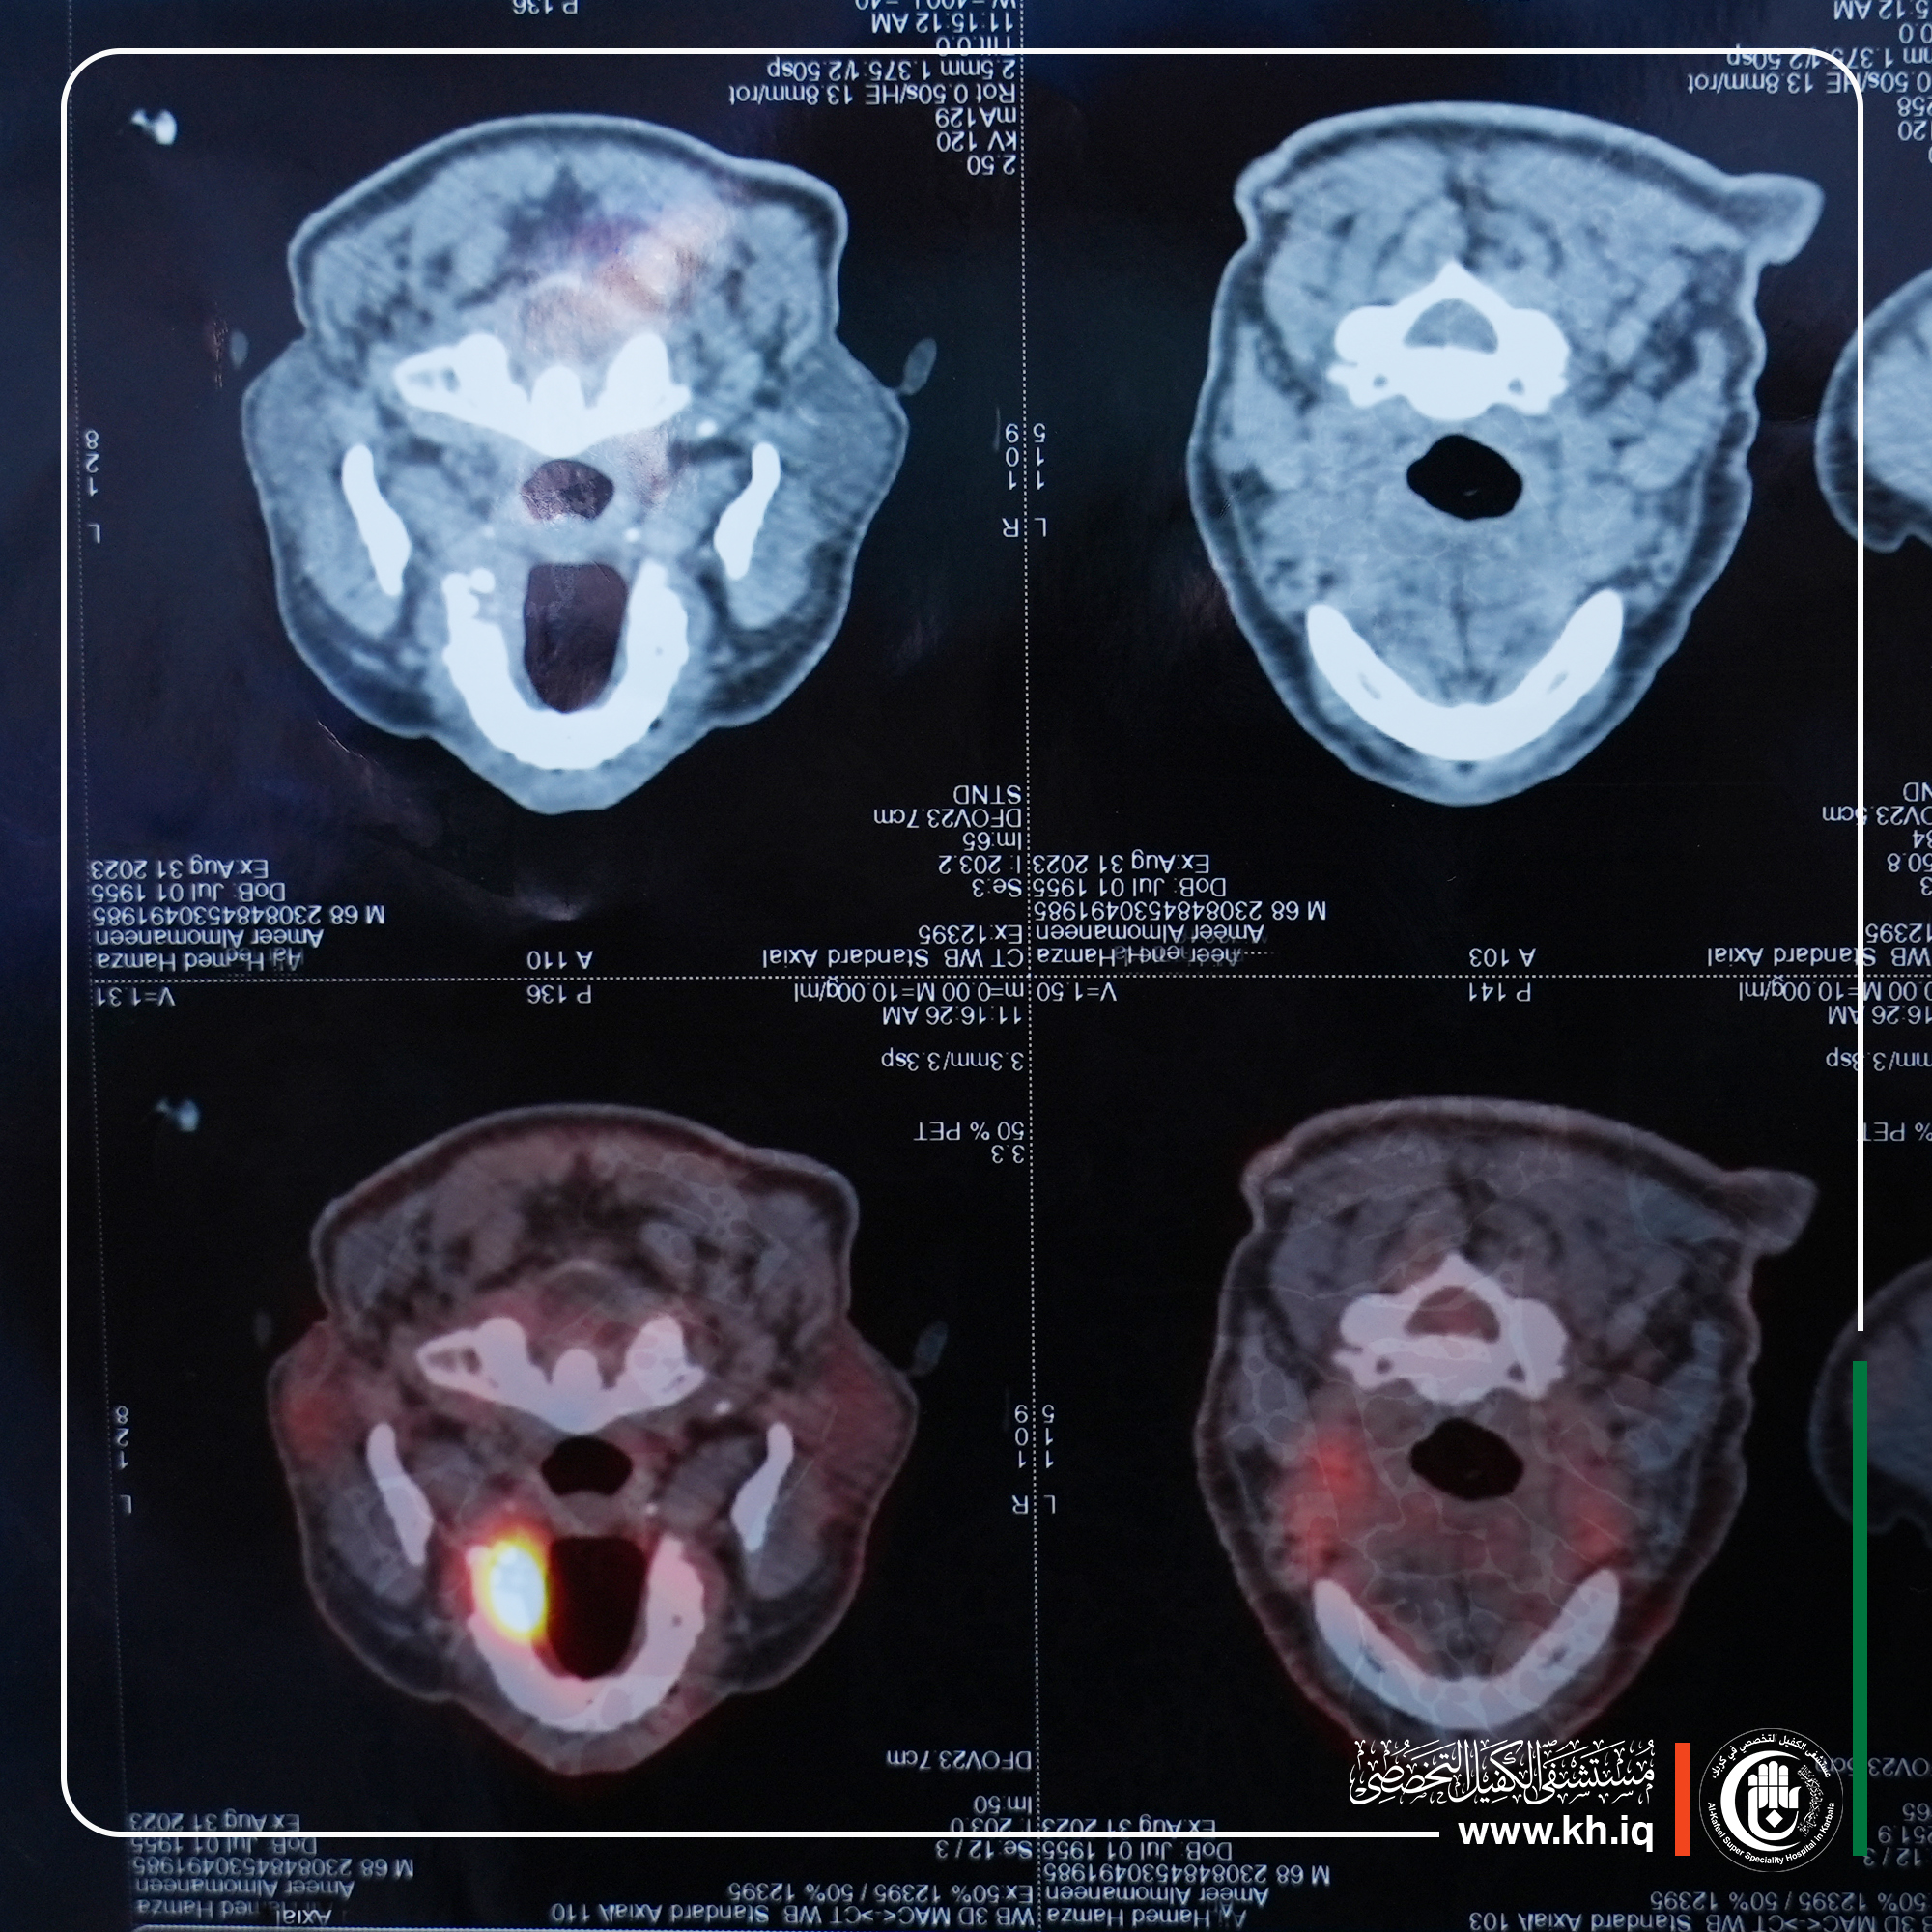

وقال اختصاصي جراحة الوجه والفكين، د. رضوان الطائي، إن عملية متقدمة أجريناها لمريض في العقد السادس من العمر يعاني من وجود ورم سرطاني في اللهاة ممتداً الى الفك الأعلى بالإضافة الى البلعوم ومنتشراً على الغدد اللمفاوية الموجودة على الرقبة والشرايين الرئيسية.

وذكر الطائي أجريت العملية بدقة عالية تمكنا خلالها من استئصال الورم السرطاني من اللهاة بشكل كامل بالإضافة الى أخذ مسافة أمان من الخد والأنف بالإضافة الى ارضية محجر العين وترقيع هذه المناطق عن طريق سدلات مع بزل الغدد اللمفاوية وعزل الشرايين والأوعية الدموية الممتدة للدماغ عن طريق الرقبة، مؤكداً إن هذه العمليات المتقدمة سابقاً لم تكن تجرى داخل العراق لكن بوجود مستشفيات متطورة مثل مستشفى الكفيل اغنى المرضى عن السفر للعلاج خارج البلد.